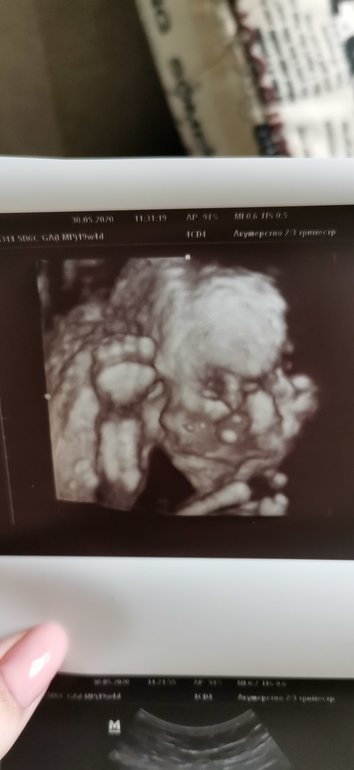

В субботу прошли второй скрининг, все хорошо, сказали, что малыш активный, но я и так это чувствую 😂 зато не переживаю, что это гипоксия.

Врач решила показать нам личико малыша, по-моему, на меня похож, но муж, естественно, не согласен 😂